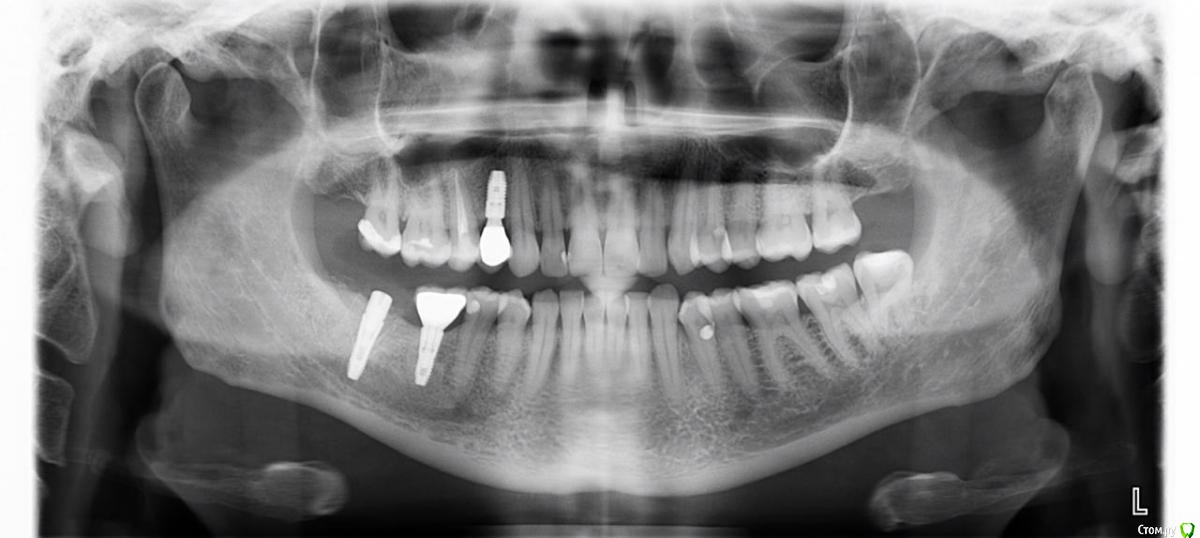

mediis Опубликовано 24 июня, 2019 Поделиться Опубликовано 24 июня, 2019 Здравствуйте! 07.06.2019 мне удалили одновременно два зуба - 7-й и 8-й на нижней челюсти справа с одномоментной имплантацией 7-го. Во время анестезии я почувствовала пронизывающую боль, как электрическим током в районе 2 и 3-го зубов снизу справа, как будто игла задела нерв. После окончания действия анестезии и до настоящего момента отсутствует чувствительность этих 2,3,4-го зубов, онемела правая половина нижней губы и часть подбородка в этой зоне. И еще, появился белый треугольник на лице в районе носогубной части. Нечувствительные зубы ломит, есть ощущение распирания в районе импланта.Посмотрите пожалуйста снимок, вернётся ли чувствительность? Что делать? Врач уверяет, что все отлично, порекомендовал пропить нейромультивит. К сожалению, могу отправить только ссылки на файл. До операции - https://cloud.mail.ru/stock/2UZAKrd1ainvCmjJm9cKMi9Y После - https://cloud.mail.ru/stock/GfEAhknzD8Q61eww4mqRcGc2 Ссылка на комментарий

mediis Опубликовано 24 июня, 2019 Автор Поделиться Опубликовано 24 июня, 2019 (изменено) Вот снимки после удаления 7-го и 8-го и одномоментной имплантантации 7-го и до операции. Изменено 24 июня, 2019 пользователем mediis Ссылка на комментарий

red_butler Опубликовано 25 июня, 2019 Поделиться Опубликовано 25 июня, 2019 я бы убрал имплант в позиции 4.7 2 Ссылка на комментарий

Bier Опубликовано 26 июня, 2019 Поделиться Опубликовано 26 июня, 2019 Да, имплантат нужно убрать Ссылка на комментарий